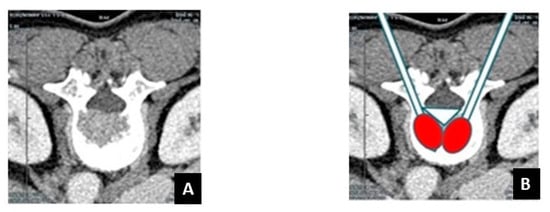

Figure 1. Limits of the use of conventional radiofrequency straight needles for the treatment of difficult-to-reach vertebral metastases. (A) Breast cancer metastasis in a 61-year-old patient. Axial CT scan shows a lytic lesion of in the posterior wall of the vertebral body L2 with cortical disruption. (B) Conventional RFA with straight needles is not able to ablate the entire lesion (white triangle).